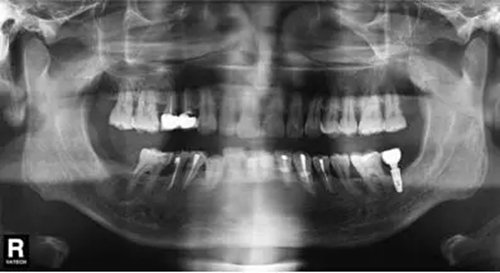

圖9 拔除47植入骨粉膠原塞曲面體層片

微創(chuàng)拔除47后,植入骨粉膠原塞(圖7~9);3個(gè)月后CBCT分析骨質(zhì);行47種植牙修復(fù)術(shù)。